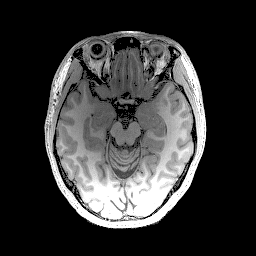

In the first set of evaluations, we considered the reconstruction of an MR image from -undersampled k-space data. The gold-standard magnitude and phase images, which were obtained from a real fully-sampled in vivo T1-weighted MRI acquisition with in-plane matrix size, are shown in Fig. 1. This figure also shows the k-space sampling mask (corresponding to undersampling) that we used to simulate an accelerated acquisition.